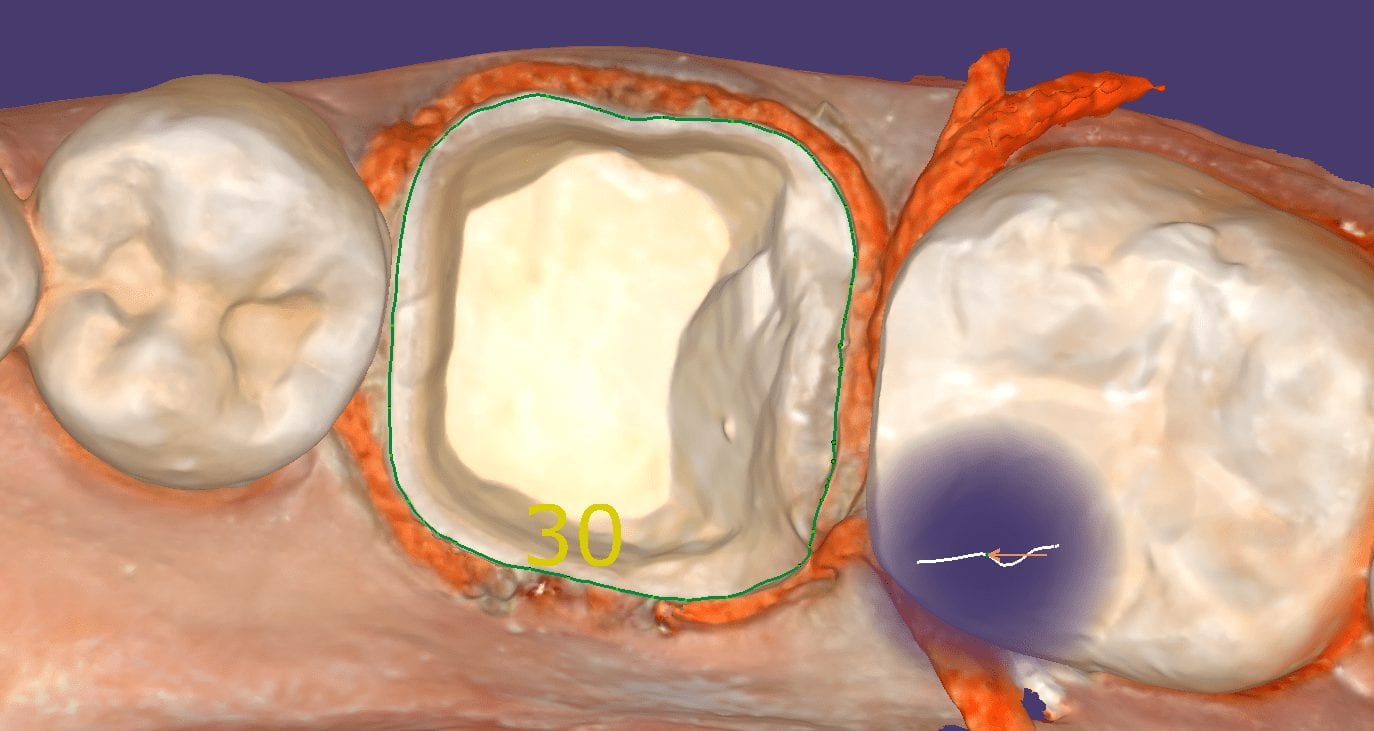

January 15, 2019A new feature coming soon to Medit I500 is localized High Definition Scanning. There are two modes you can scan and save the models in; Normal and High Definition. In […]

A new feature coming soon to Medit I500 is localized High Definition Scanning. There are two modes you can scan and save the models in; Normal and High Definition. In […]